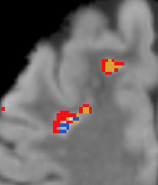

We obtained gray matter, white matter, CSF, and lesion maps for each subject based on T1-weighted, T2-weighted, and FLAIR images. Ultimately, the NA-MIC Kit will provide a workflow for individual and group analysis of lesions. It will be implemented as a set of Slicer3 modules that can be used interactively within the Slicer3 application as well as in batch on a computing cluster using BatchMake.

- Scully M, Anderson B, Lane T, Gasparovic C, Magnotta V, Sibbitt W, Roldan C, Kikinis R and Bockholt HJ (2010) An automated method for segmenting white matter lesions through multi-level morphometric feature classification with application to lupus. Front. Hum. Neurosci. 4:27. doi:10.3389/fnhum.2010.00027. Available here